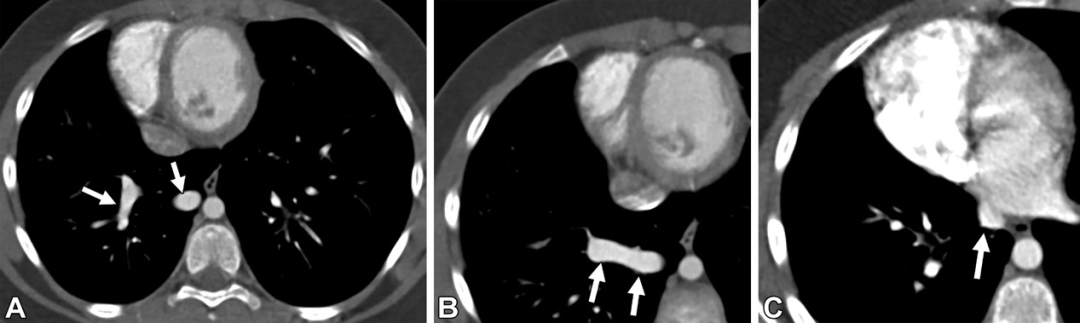

肝肺综合征。72岁男性,气短。(A,B)按照肺栓塞扫描程序进行的轴位增强CT,可见双肺下叶扩张的胸膜下血管(黑色箭头),扩张的结节形及螺旋形血管(白色箭头)与胸膜相连。(C)上腹部CT图,可见肝表面呈结节状(白色虚线箭头),符合肝硬化表现。(D)轴位CT,可见左心房的右侧早期显影(白色星号),符合右向左分流表现。以上表现符合肝肺综合征。